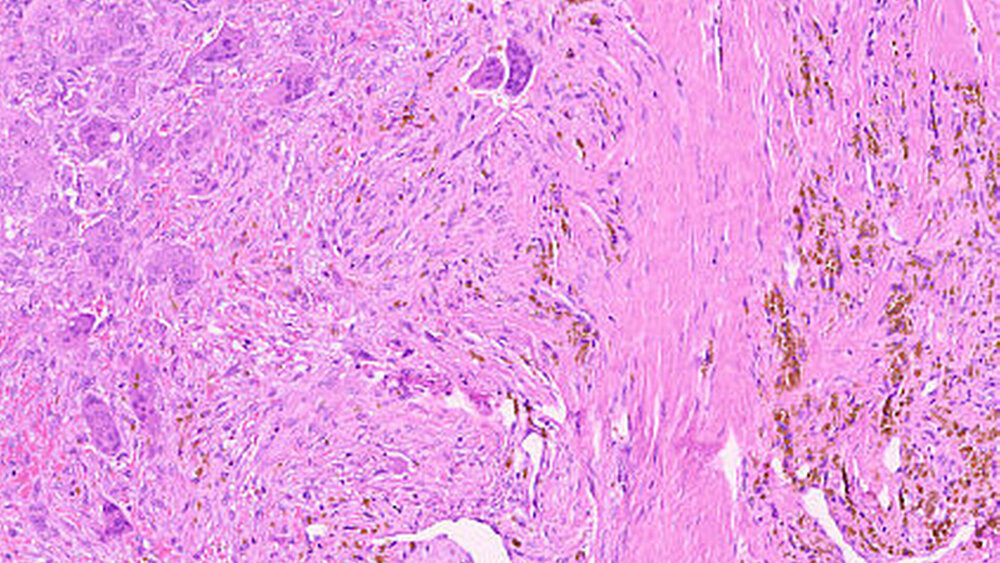

Die histopathologische Untersuchung ergab eine riesenzellbildende Läsion, so dass eine rein histopathologische Unterscheidung zwischen zentralem beziehungsweise peripherem Riesenzellgranulom und einem braunen Tumor nicht möglich war. Die weiterführende laborchemische Diagnostik ergab ein erhöhtes Parathormon im Serum 148,2 pg/ml (Norm: 15,0 bis 68,3 pg/ml) und ein normales Serumkalzium von 2,38 mmol/l (2,20 bis 2,55 mmol/l), so dass in Zusammenschau aller Befunde von einem braunen Tumor bei renal sekundärem Hyperparathyreoidismus auszugehen ist.

Histopathologisch zeigen braune Tumore einen ähnlichen Aufbau wie Riesenzellgranulome beziehungsweise die solide Variante der aneurysmatischen Knochenzyste. Alle zeichnen sich durch das Vorhandensein von gefäßreichem Granulationsgewebe aus, in das zahlreiche mehrkernige osteoklastäre Riesenzellen eingebettet sind [Neville, 2009]. Hämosiderinbeladene Makrophagen führen zur typischen rötlich-braunen Farbe, die dem Tumor den Namen gegeben hat. Differenzialdiagnostisch bedarf es dann der laborchemischen Abklärung, um die Dia-gnose eines braunen Tumors stellen zu können. In der Regel werden Parathormon, Kalzium und Phosphat bestimmt.